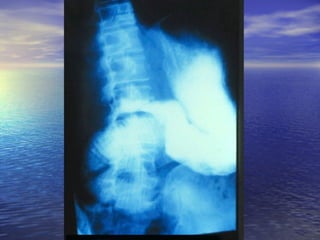

• Estudio radiológico consiste enEstudio radiológico consiste en

administración de 250ml oral de bario y laadministración de 250ml oral de bario y la

obtención de radiografías seriadas delobtención de radiografías seriadas del

intestino, realizadas a intervalos, hastaintestino, realizadas a intervalos, hasta

que el contraste llega al cielo.que el contraste llega al cielo.